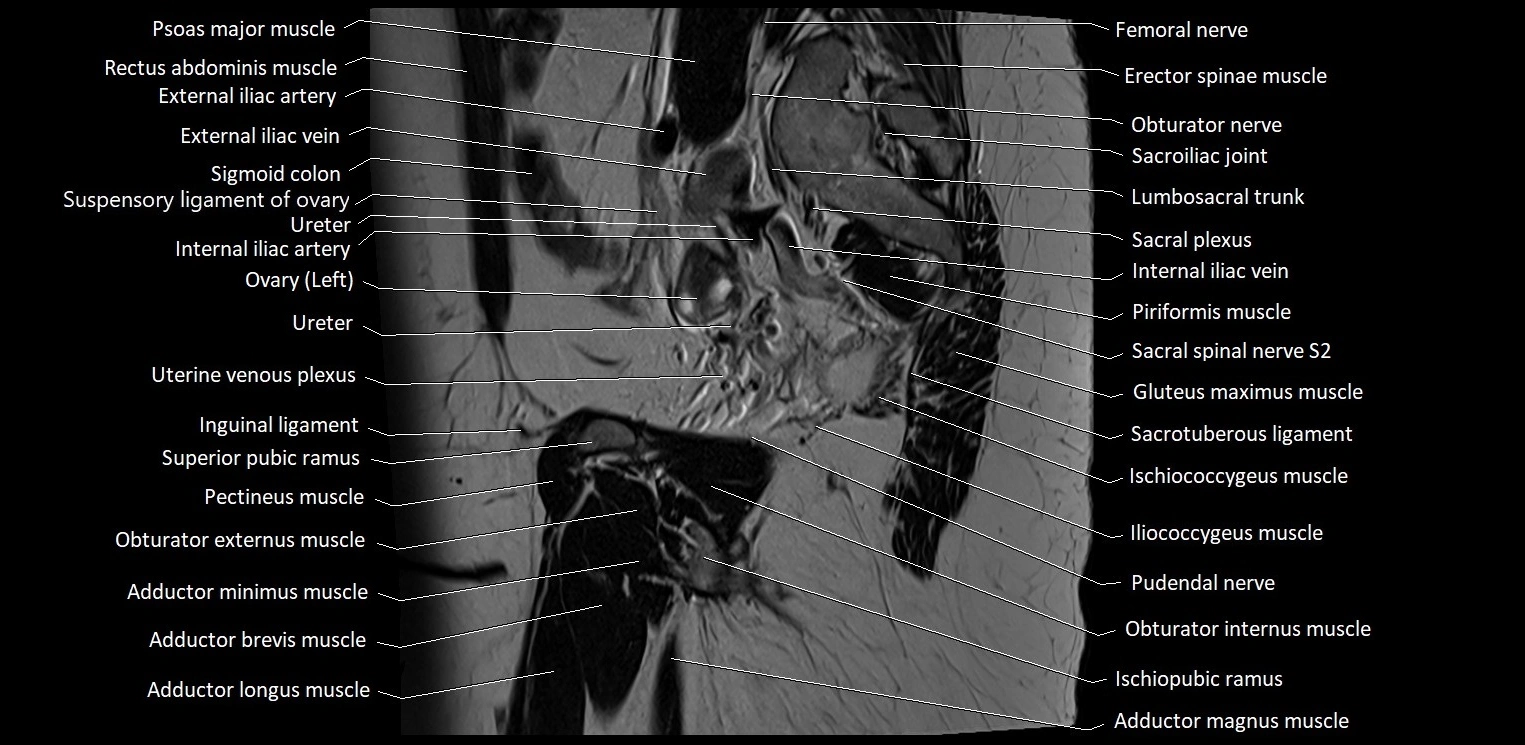

- Adductor brevis muscle

- Adductor longus muscle

- Adductor magnus muscle

- Adductor minimus muscle

- Femoral nerve

- Iliococcygeus muscle

- Inferior pubic ramus

- Inguinal ligament

- Internal iliac vein

- Ischiopubic ramus

- Lumbosacral trunk

- Obturator externus muscle

- Obturator internus muscle

- Obturator nerve

- Pectineus muscle

- Piriformis muscle

- Pubococcygeus muscle

- Pudendal nerve

- Sacral plexus

- Sacroiliac joint

- Sacrotuberous ligament

- Sartorius muscle

- Superior pubic ramus